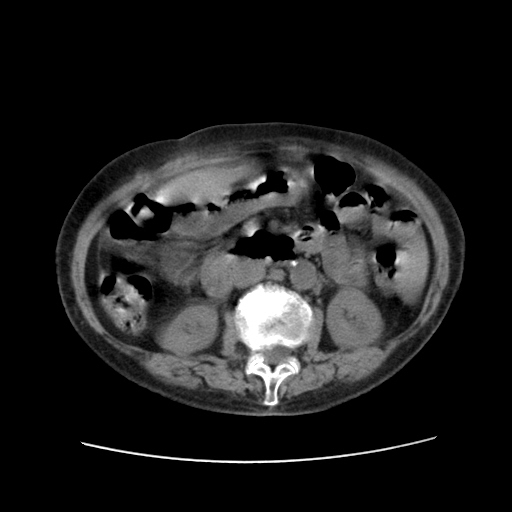

女,77.无不适

肝脏变异、异位胆囊,肝右叶肝内胆管结石并肝内胆管扩张。

肝右叶肝内胆管结石并肝内胆管扩张。

肝右叶肝内胆管结石并肝内胆管扩张

胆总管扩张

肝右叶肝内胆管结石并肝内胆管扩张。胆总管下段梗阻,考虑壶腹部占位。

右侧肝内胆管局限性扩张,其内密度不均匀,扩张的胆管壁增厚,考虑肝内胆管炎合并结石可能性大

肝右叶肝内胆管结石并肝内胆管扩张。胆总管下段梗阻,考虑壶腹部占位。支持